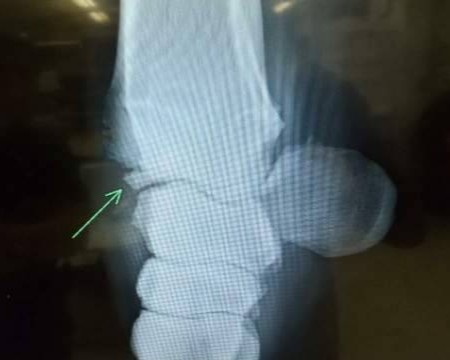

中央競馬ではデビュー以来コンスタントに出走してきましたが、2025年7月19日のレース中に左前橈骨遠位端剥離骨折を発症し、獣医師による診断の結果、全治6カ月との所見を受けました。今後については休養を挟んでの再起も検討いたしましたが、関係者一同で慎重に協議を重ねた結果、断腸の思いではありますが、今回のオークションに上場させていただく運びとなりました。現役続行および復帰に際しては剥離骨片の除去を推奨されておりますが、手術は行っておりません。また、骨折部周囲には骨膜の造成も確認されている旨、あらかじめご承知おきくださいますようお願いいたします。

※2025年7月19日の競走中に左前橈骨遠位端剥離骨折を発症。事故見舞金9号(競走中の事故により事故発生の日から6カ月以上出走できなくなった場合)の適用を受けています。